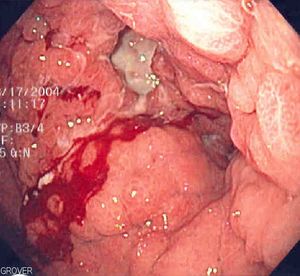

내출혈은 신체 내부의 혈관이 손상되어 혈액이 체내로 새어 나가는 상태를 의미한다. 주요 원인은 외상이며, 관통 외상과 둔탁 외상으로 구분된다. 고혈압, 동맥류, 혈액 질환 등 비외상성 원인으로도 발생할 수 있다. 증상으로는 어지럼증, 피로, 빠른 심박수 등이 나타나며, 심한 경우 저혈량 쇼크로 이어질 수 있다. 진단은 신체 검사, 초음파 검사, CT 촬영 등을 통해 이루어지며, 치료는 출혈을 멈추는 것이 중요하며, 수액 보충 및 수혈이 필요할 수 있다.

고혈압, 동맥류, 소화성 궤양, 또는 자궁외 임신의 결과로 인한 혈관 파열이 내출혈을 유발할 수 있다.[8] 암, 혈액 질환, 비타민 K 결핍, 그리고 에볼라, 뎅기열 또는 마버그 바이러스병과 같은 드문 바이러스성 출혈열 등도 내출혈과 관련이 있다.[9]

혈뇨, 검은 변, 선홍색 변, 코피, 멍, 토혈 등 출혈 부위에 따라 특징적인 증상이 나타날 수 있다.[1]3. 3. 쇼크